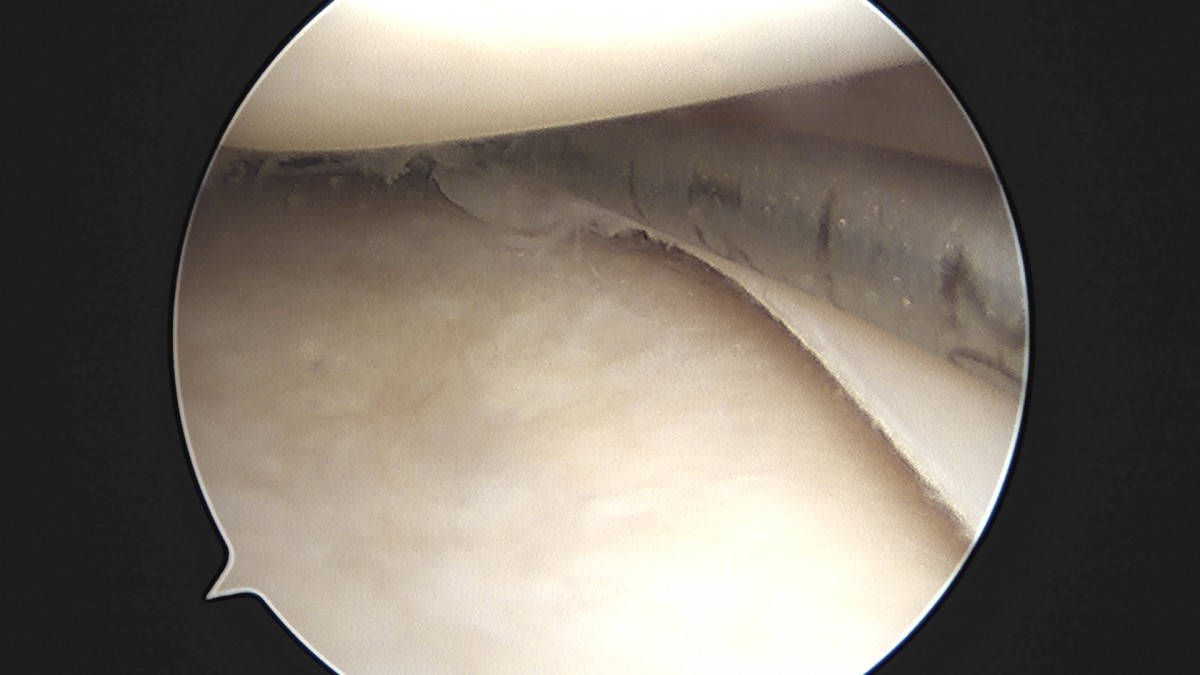

이재상원장님 무릎 반월상 연골판 절제술 고기O 환자

dae765e4d9ac96aee867c9d6292d8784_1758005091_6618.jpg